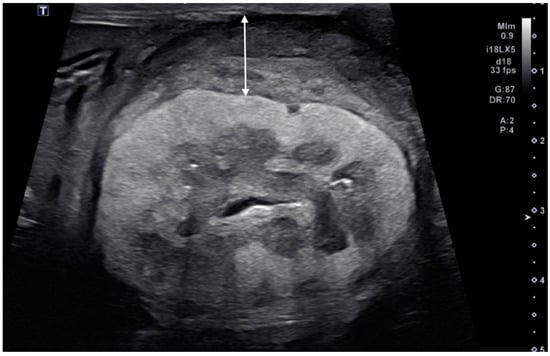

| right | circumferential | 13.2 | hetero | hetero | irregular | irregular | yes | yes | abnormal | completely effaced | 1.9 | yes | yes | no | Primary Renal Carcinoma | ||||